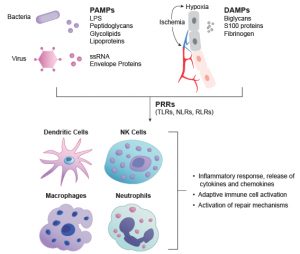

Como vimos no resumo da semana passada, as células dendríticas (DCs) são especializadas na captura e apresentação de antígenos para os linfócitos, e por sua vez, são consideradas uma ponte entre a imunidade inata e a adaptativa, justamente por serem atraídas e ativadas por elementos da resposta inata e viabilizarem a sensibilização de Linfócitos T da resposta imune adaptativa.

Essas, residem em tecidos periféricos, como pele, fígado e intestino, onde capturam antígenos e se tornam ativadas. Após isso, tais células serão direcionadas e migrarão diretamente para os linfonodos regionais, que são responsáveis por processar e apresentar antígenos proteicos ou lipídicos aos LTs (5, 7).

Sabe-se que DCs imaturas são altamente eficientes na captura de antígenos, enquanto as maduras são muito eficientes na apresentação.Os antígenos capturados são processados dentro da célula e apresentados em sua superfície, inseridos em moléculas do MHC. Em geral, antígenos proteicos são apresentados por moléculas MHCs clássicas, de classes I e II (5, 7)